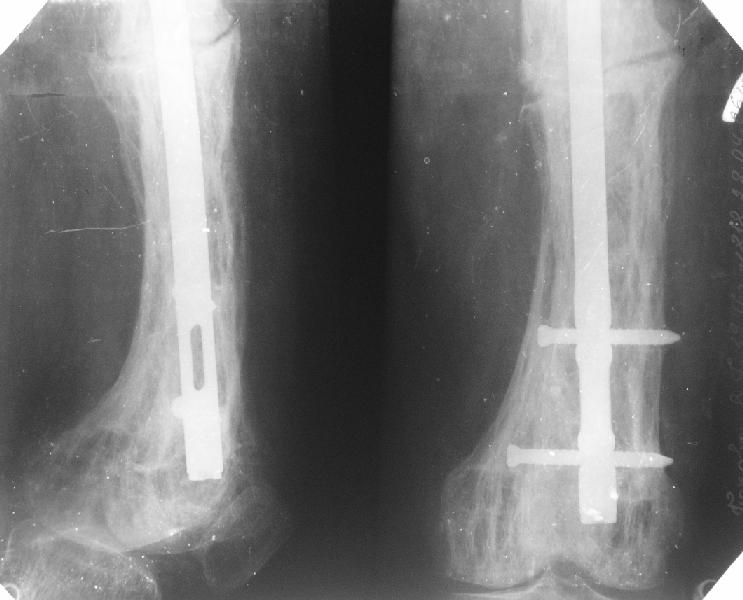

Еще один пример. Пациентка с юга России, прислала рентгенограммы через год. На сегодня прошло 2 г. 8 мес. после операции. Несмотря на не очень убедительный процесс сращения, пациентка ходит. Учитывая остеопороз при Педжете, решили, что динамизировать вообще не нужно.

При переломах на фоне болезни Педжета металлоконструкция часто служит эндопротезом, несущим нагрузку. Динамизация индивидуальна,- по рентген-динамике. Основной упор- на медикаментозную терапию- см. канд. дисс. Колондаева А.Ф.

Стержень можно было бы поставить подлиннее.